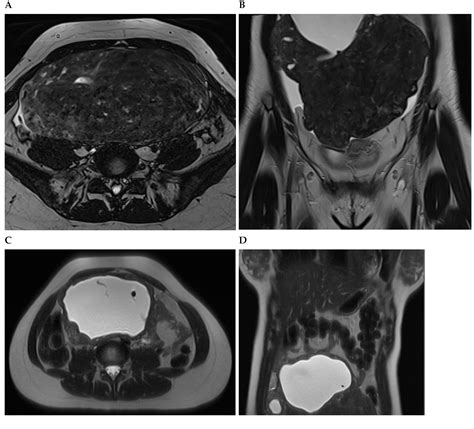

Diagnosing uterine myoma degeneration involves a combination of medical history, physical examination, and imaging tests. The diagnostic process typically includes:

• Imaging Tests: Ultrasound, MRI, or CT scans to visualize the fibroids and assess the extent of degeneration.